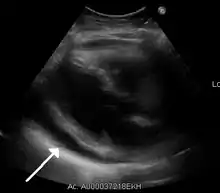

The diagnosis of tamponade can be confirmed with trans-thoracic echocardiography (TTE), which should show a large pericardial effusion and diastolic collapse of the right ventricle and right atrium. Chest X-ray usually shows an enlarged cardiac silhouette ("water bottle" appearance) and clear lungs. Pulmonary congestion is typically not seen because equalization of diastolic pressures constrains the pulmonary capillary wedge pressure to the intra-pericardial pressure (and all other diastolic pressures).

Diffuse ST elevation in a young male due to myocarditis / pericarditis

An ECG showing pericarditis. Note the ST elevation in multiple leads with slight reciprocal ST depression in aVR.

The preferred initial diagnostic testing is the ECG, which may demonstrate a 12-lead electrocardiogram with diffuse, non-specific, concave ("saddle-shaped"), ST-segment elevations in all leads except aVR and V1[11] and PR-segment depression possible in any lead except aVR;[11] sinus tachycardia, and low-voltage QRS complexes can also be seen if there is subsymptomatic levels of pericardial effusion. The PR depression is often seen early in the process as the thin atria are affected more easily than the ventricles by the inflammatory process of the pericardium.